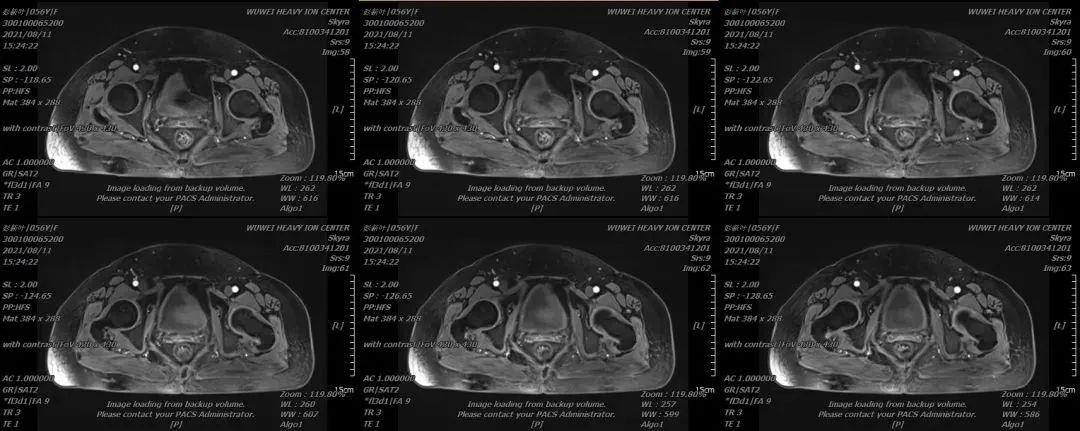

2021年8月重离子治疗后5月后MR

该患者阴道流血停止,妇科查体及盆腔核磁疗效评价CR,目前该患者已完成24个月随访,肿瘤无复发及转移发生。